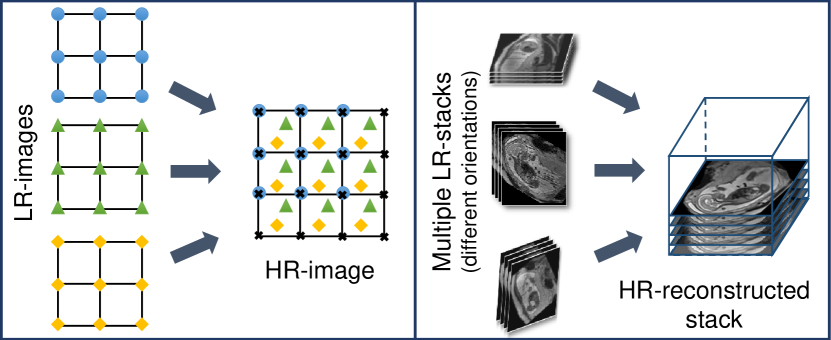

Slice-to-volume registration (SVR): SVR combined with super-resolution image reconstruction techniques [11] can be applied to compensate motion between single slices by reconstructing a high-resolution (HR) image from multiple, overlapping low-resolution (LR) images, as shown in Fig. 2. To provide a sufficiently high number of samples for such an approach, multiple stacks of 2D-slices need to be acquired, ideally in orthogonal orientations. A simple LR HR reconstruction model [11] can be formalized as:

Most motion compensation approaches for fetal MRI are based on SVR techniques that aim to obtain a motion-free and high resolution volume of a fetal target region. Registration of individual 2D slices with a higher resolution 3D volume [22] is the core approach of these algorithms. SVR methods assume that all acquired image stacks are centered at a specific fetal organ (e.g., brain, thorax) and cover three orthogonal image directions. Fig. 3 shows the core elements of SVR and the contribution of previous frameworks from the literature.